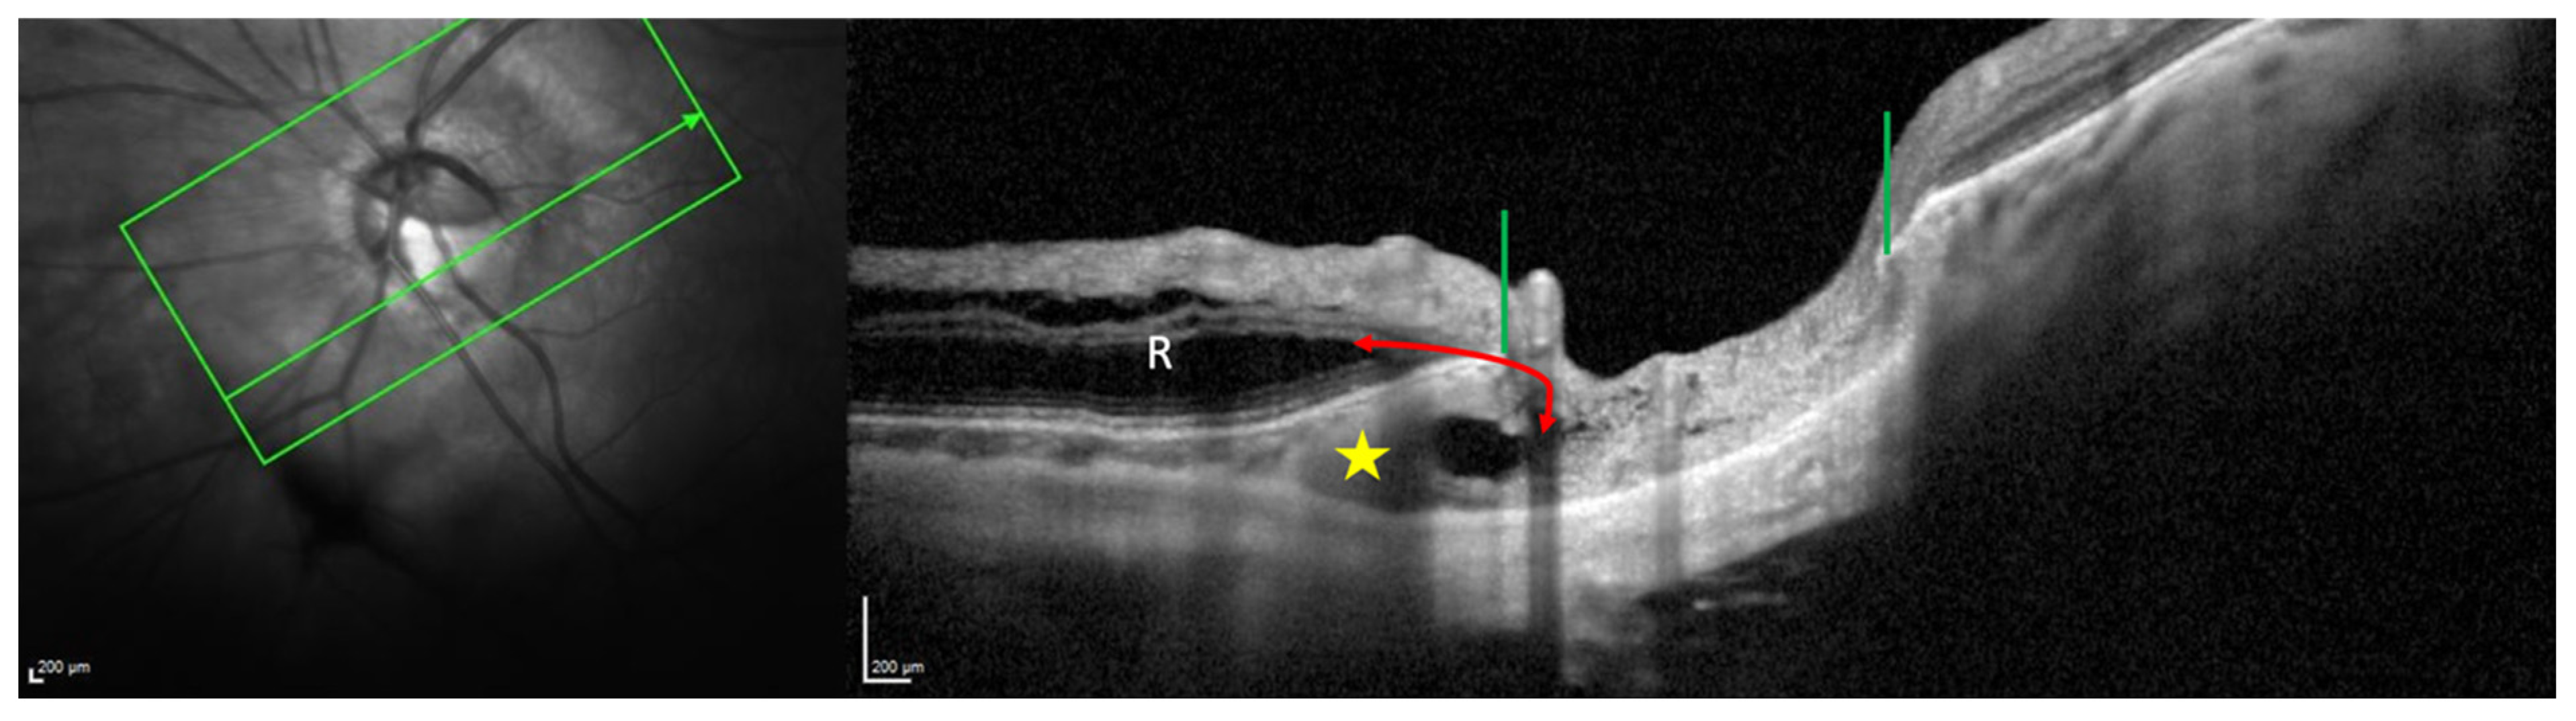

6.2. Macular Abnormalities and PICC

8.2. Fluidic Considerations

8.3. Mechanical Considerations

8.3.1. PICC as a Complication of Peripapillary Staphyloma

8.3.2. PICC as a Complication of Myopic Tilted Disc and Myopic Conus

8.3.3. PICC as a Complication of the Optic Nerve Sheaths Traction